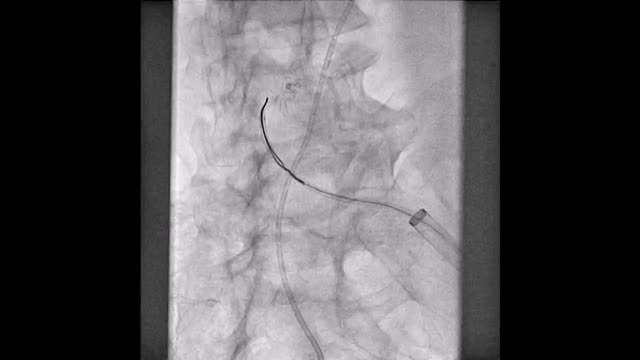

El paciente se traslada a la sala de hemodinamia donde se intenta la extracción del dispositivo. Se utilizan diferentes catéteres lazo de 10, 25 y 30 mm, así como lazos de fabricación con guías largas y cortas intentando movilizar el dispositivo desde diferentes accesos vasculares (acceso bifemoral 6 y 18 Fr y radial 6 Fr) (figuras de la 1 a la 4). Se produce como complicación disección de aorta abdominal con extensión a arteria ilíaca común derecha (figuras 5 y 6) y pérdida total del flujo en extremidad inferior ipsilateral con signos y síntomas de isquemia arterial aguda, por lo que el paciente es trasladado de forma urgente al quirófano de angiología y cirugía vascular. Se realiza disección de aorta abdominal infrarrenal vía laparotomía media con aortotomía longitudinal en el lugar de la localización del cuerpo extraño visualizándose el dispositivo migrado anclado a la íntima-media de la pared arterial. Se procede a su extracción y posteriormente se realiza cierre de aortotomía con parche de pericardio bovino fijando la disección y corrigiendo así el defecto (figuras de la 7 a la 9). El paciente sale de quirófano con pulso pedio bilateral y excelente perfusión distal.